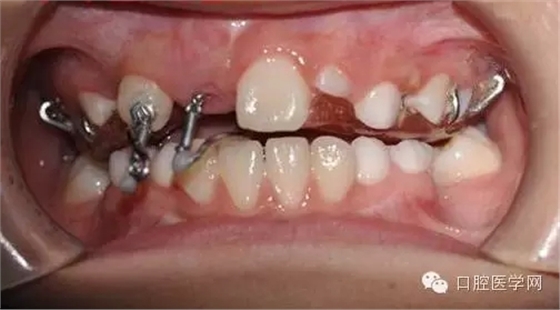

帶入口內(nèi)調(diào)整吊桿方向加輕力:

(咬合調(diào)整好,加輕力激活)

每周復(fù)診:清洗,加力,適當(dāng)調(diào)整吊桿方向